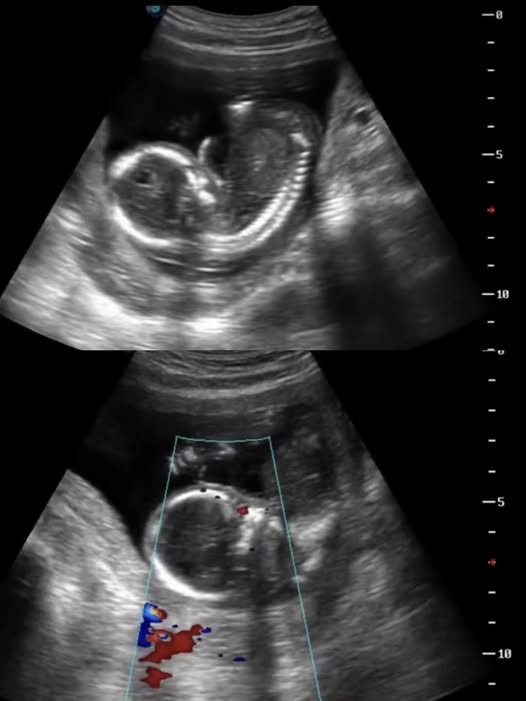

Đến tối cùng ngày, chị nhận thấy thai nhi không còn cử động. Ngay lập tức, gia đình đưa chị đến phòng khám gần nhất, nhưng mọi nỗ lực đều không thể cứu vãn. Bác sĩ thông báo thai đã ngừng tim, để lại cú sốc tinh thần lớn cho người mẹ.

Cụ thể, ngồi xe lâu liên tục dễ gây mệt mỏi, tụ máu vùng chậu, rối loạn tuần hoàn máu, từ đó ảnh hưởng đến việc cung cấp oxy và dưỡng chất cho thai nhi. Với những thai phụ có tiền sử dọa sảy, dọa sinh non hoặc thai yếu, việc di chuyển xa càng tiềm ẩn rủi ro cao.

Bên cạnh đó, làm việc quá sức, đứng lâu, cúi gập người, bê vác nặng hoặc căng thẳng kéo dài có thể làm tăng co bóp tử cung, dẫn đến dọa sảy thai, sinh non hoặc thai lưu. Stress tâm lý cũng là yếu tố nguy hiểm, bởi nó có thể ảnh hưởng đến nội tiết và gián tiếp tác động xấu đến thai nhi.